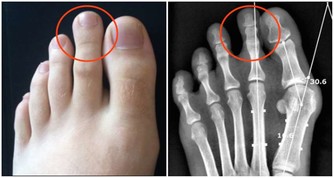

四、腳指甲下凹指甲變蒼白

我們經常會發現我們的腳指甲會出現下凹的情況,用手摸在腳指甲上的感覺是凹凸不平的。這同樣也是由於營養不良和自身貧血的情況引起的。由於在生活中我們吃的食物過於油膩導致營養不良,身體中的維生素和膳食纖維得不到合理的補充,以及體內缺少足夠的血紅蛋白。反應在我們腳上面,就是我們的腳趾甲會出現下凹和腳趾甲缺少血色。

面對這樣的情況,我們的應對措施就是我們多多的吃一些水果,蔬菜,粗糧等等補充自己的維生素和膳食纖維,還有多食用一些補血的水果,肉類等等。營養得到補充,身體自然而然的不會出現這樣的徵兆。